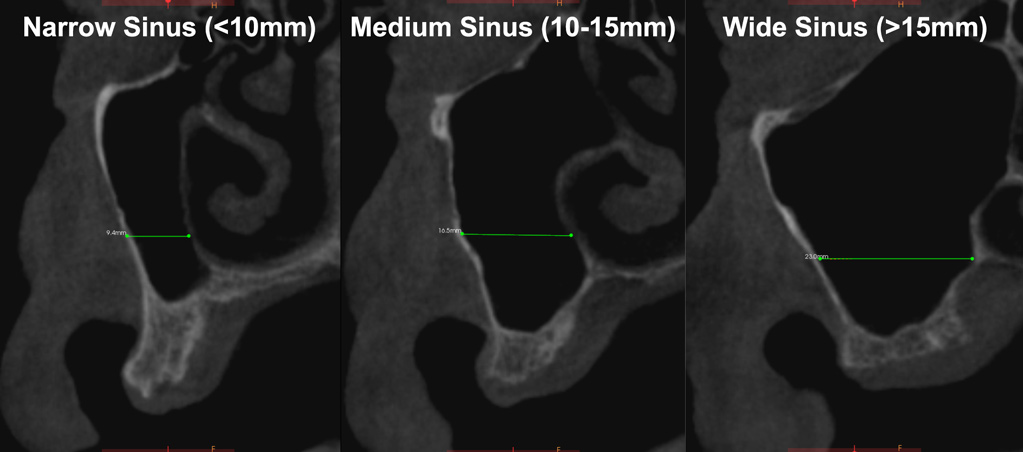

One reported limitation of using PRF alone for sinus augmentation procedures is its use in wide sinuses. Avila et al demonstrated that lateral sinus augmentation procedures performed with an allograft in narrow sinuses (<10 mm) and medium sinuses (10 mm to 15 mm) demonstrated roughly three times more vital bone after a 6-month healing period when compared with wide sinuses (>15 mm) (Figure 4).24 In response to these findings and the clinical experiences of numerous oral surgeons using PRF alone for sinus augmentation procedures, it has been recommended that sinuses >15 mm be regenerated in a combination approach with a bone grafting material. Therefore, all sinuses greater than 15 mm should be regenerated using PRF cut into small fragments with a bone grafting material (Figure 5 and Figure 6).

Fig 4. Cone-beam computed tomography of morphological size differences between narrow (<10 mm) (left), medium (10 mm to 15 mm) (center), and wide (>15 mm) (right) sinuses. The bucco-palatal distance is a predictable gauge for determining when to use PRF alone versus in combination with a bone grafting material.